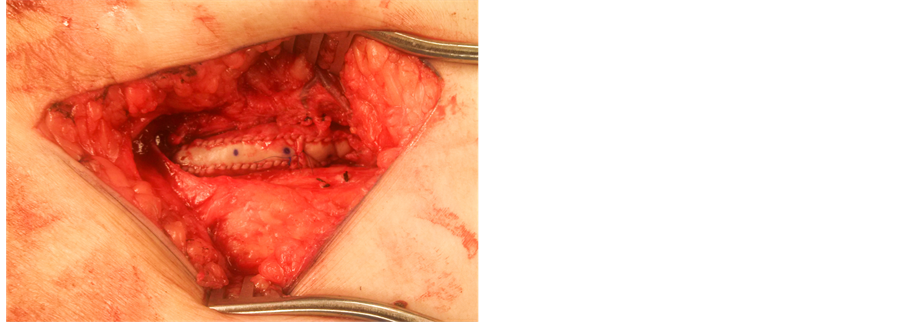

Endoprosthesis, expanded polytetrafluoroethylene (ePTFE) liner attached to an external nitinol stent) was then deployed in the proximal SFA, under direct supervision, without the aid of fluoroscopy. The proximal end of the stent is positioned to be deployed at the distal end of the arteriotomy (Figure 3). After completion of the endarterectomy (Figure 4), a Bovine pericardium patch was then used to repair the arteriotomy (Figure 5). A completion arteriogram was then performed in cases where fluoroscopy was needed for treatment of other lesions (Figure 6).

Figure 3. Deployment of a Viabahn stent under direct visualization.

Figure 4. Completed endarterectomy.